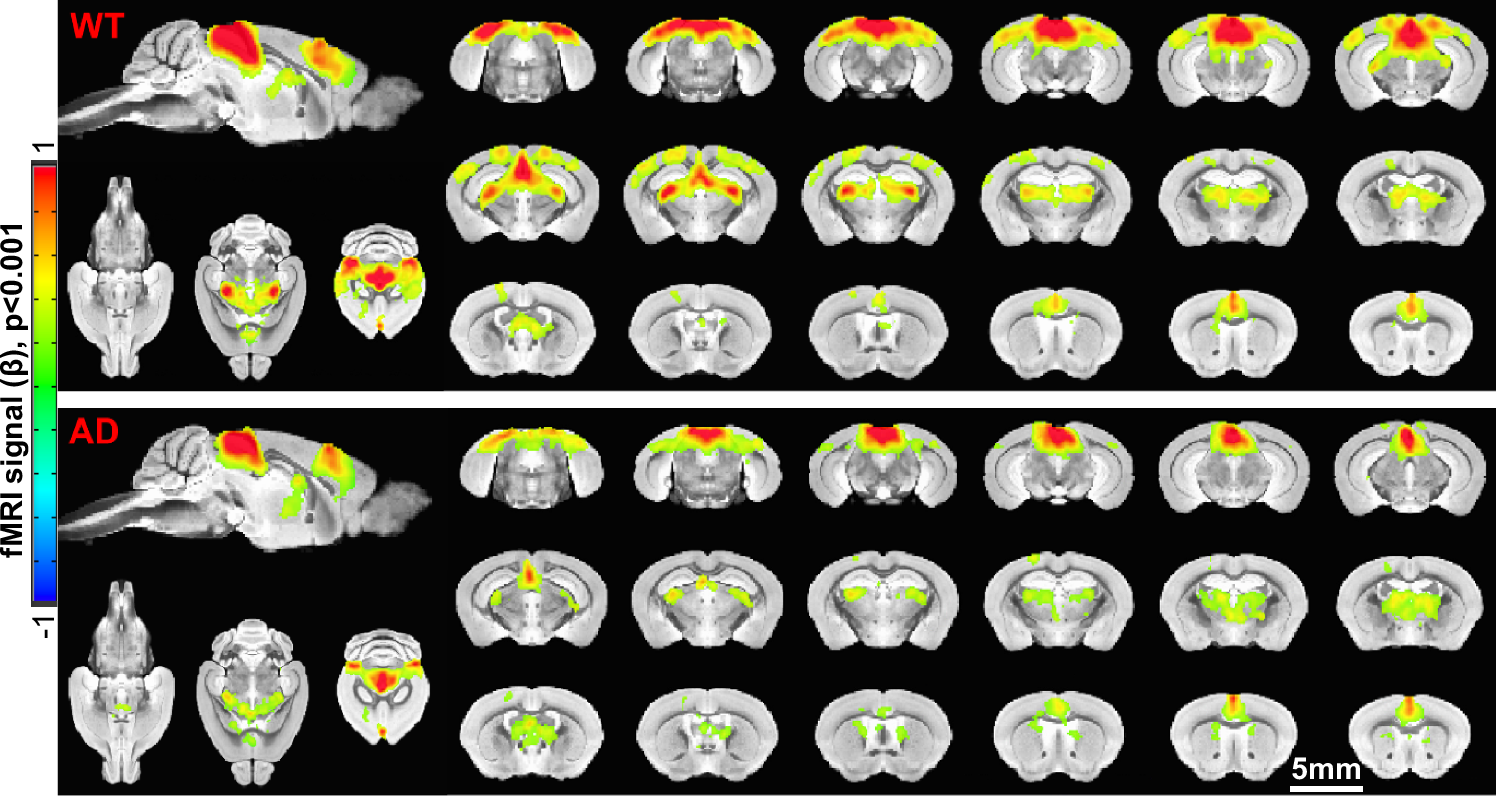

Fig. 2: The brain-wide BOLD functional maps of awake wild-type (WT) and Alzheimer’s disease (AD) mice with visual stimulation.

The functional maps of awake mice show significant BOLD activation in the visual cortex (VC), superior colliculus (SC), retrosplenial cortex (RSP), lateral geniculate nucleus (LGN), and anterior cingulate area (ACA) from both WT (upper panel) (n = 13 mice with 58 trials) and AD (lower panel) mice (n = 9 mice with 60 trials; two-sided t-test p < 0.001, FDR < 0.01, minimum cluster size = 200 voxels). Source data are provided as a Source Data file.